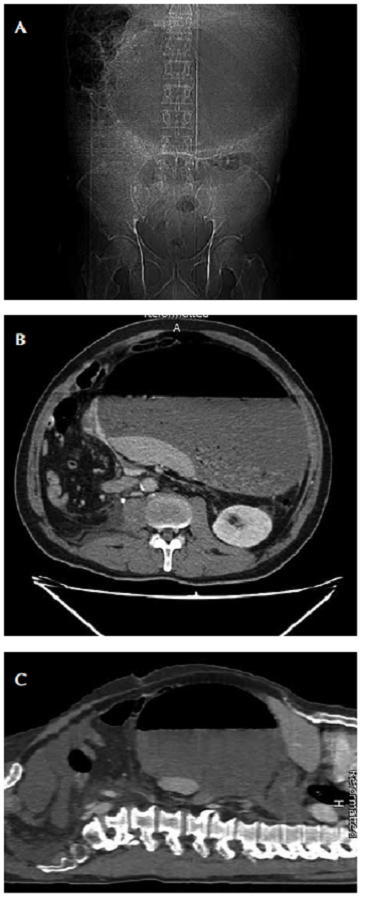

En el cuadro hemático se encontró: 15.200 leucocitos por mm3 /μ, neutrófilos 86 %, linfocitos 5 %; hemoglobina, 16 g/dl, hematocrito 51,8 % y 219.000 plaquetas por mm3 /μl En la radiografía simple de abdomen se observó aumento anormal del tamaño de la cámara gástrica (figura 1A). Ante la sospecha de un cuadro clínico obstructivo, se practicó una tomografía computadorizada (TC) abdominal, en la que se apreciaba un gran nivel hidroaéreo en la cámara gástrica (figura 1, B y C). El paciente evolucionó de forma tórpida, con aumento del dolor abdominal, taquicardia y signos de irritación peritoneal, por lo que se decidió someterlo a una laparotomía exploratoria por abdomen agudo quirúrgico.

El hallazgo clásico del vólvulo gástrico agudo en la radiografía abdominal simple, es una solaburbuja de gas esférica grande, localizada en la parte superior del abdomen, la cual se observó en el primer paciente (figura 1). Generalmente, hay poco aire en el intestino distal y una característica distintiva del vólvulo órgano-axial es que el nivel hidroaéreo se encuentra en un plano horizontal cuando se ve en radiografías simples en proyección AP. En el vólvulo mesentérico-axial, el estómago se ve esférico en las imágenes tomadas en posición supina, pero se observan dos niveles hidroaéreos en proyecciones tomadas en posición vertical, con el antro situado por encima del fondo gástrico. El estudio fluoroscópico conbario oral confirma el diagnóstico y el grado de obstrucción. La TC ayuda a definir los detalles anatómicos, y confirmar la rotación del estómago y el punto de transición 23,24,25,26.